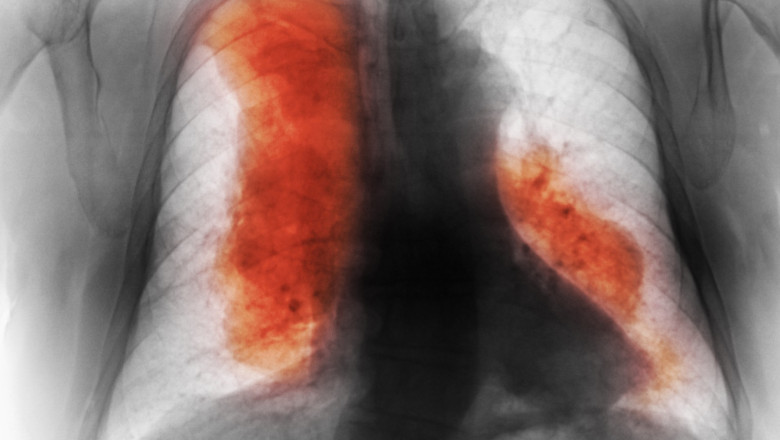

Numărul persoanelor care mor din cauza cancerului a crescut considerabil în ultimele decenii, iar până în 2050 ar putea depăşi 18,5 milioane, arată un studiu recent. Această creştere survine în ciuda progreselor medicale în tratament şi prevenirii bolii, mai ales în ţările cu venituri mai reduse.

Cercetarea publicată în jurnalul The Lancet acoperă 204 ţări şi include date despre 47 de tipuri de cancer. În 2023, s-au înregistrat aproximativ 18,5 milioane de cazuri noi şi 10,4 milioane de decese, o creştere de 74% faţă de 1990. Cancerul mamar a fost cel mai des diagnosticat, însă cel mai letal rămâne cel pulmonar.

Potrivit digi24.ro, „perspectiva pentru următorii 25 de ani indică o creştere cu 61% a cazurilor noi şi cu 75% a deceselor, dacă nu se intervine eficient”. De asemenea, aproximativ 41,7% dintre decese sunt legate de factori modificabili, precum fumatul, alimentaţia nesănătoasă şi consumul excesiv de alcool.